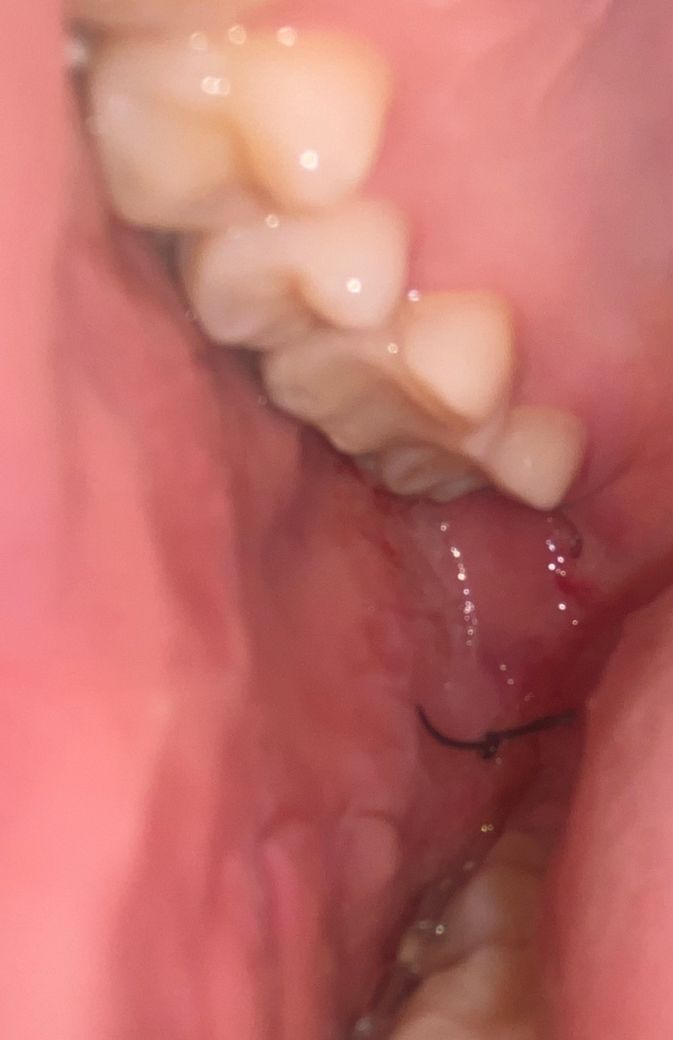

오늘 한쪽 사랑니 위아래 발치를 했는데 집 돌아와서 보니까 실밥이 볼 속에 있는 것 같아서 질문드립니다

원래 이런 경우도 있는 건가요? 아니면 내일 치과를 가봐야 할까요?

• 2번 째 사진

실밥 위치는 관계없으며 지금 위치도 정상으로 보입니다.

조금 안쪽 조금 뒷쪽 다 정상적인 범주에 속합니다.

사랑니 발치 이후에 해당 공간이 크거나 아래쪽의 경우에는 음식물 등이 저류할 수 있으므로 실로 봉합해두는 것이 일반적입니다. 현재 잇몸 상태 및 발치 부위를 보았을 때 매우 깨끗해보이며 정상적으로 보입니다. 일주일 뒤에 치과 방문 후 아래쪽에 있는 실밥을 제거하시면 될 것으로 보입니다.